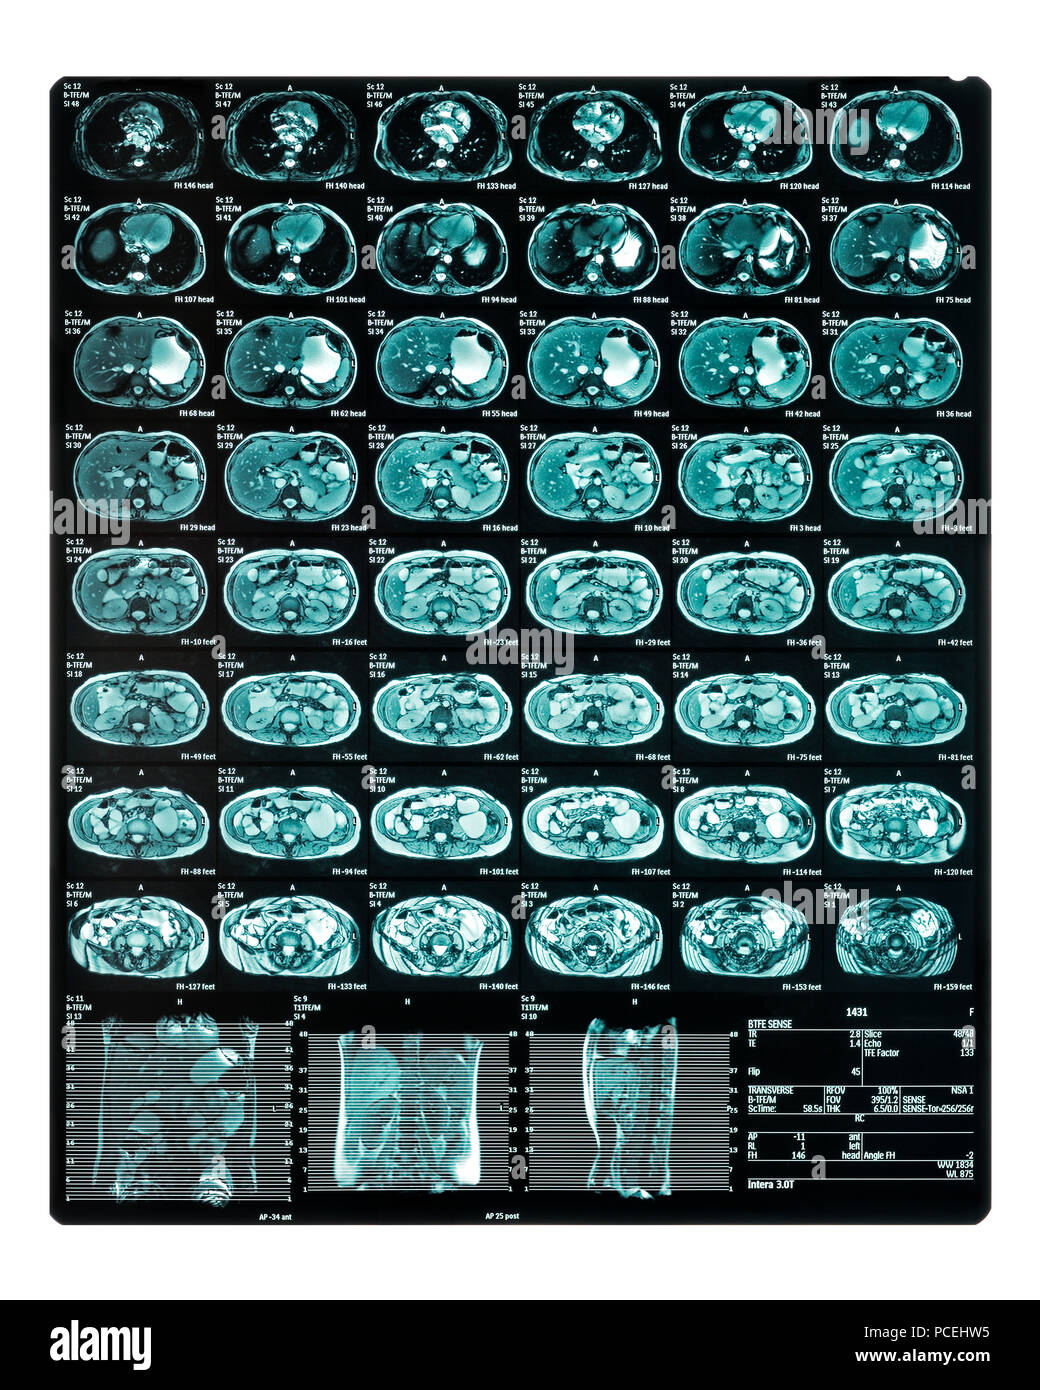

MRI Scan. MR Enterography of the small intestine a noninvasive medical test used to diagnose medical conditions of the bowels, like Crohn's disease Stock Photohttps://www.alamy.com/image-license-details/?v=1https://www.alamy.com/mri-scan-mr-enterography-of-the-small-intestine-a-noninvasive-medical-test-used-to-diagnose-medical-conditions-of-the-bowels-like-crohns-disease-image214221649.html

MRI Scan. MR Enterography of the small intestine a noninvasive medical test used to diagnose medical conditions of the bowels, like Crohn's disease Stock Photohttps://www.alamy.com/image-license-details/?v=1https://www.alamy.com/mri-scan-mr-enterography-of-the-small-intestine-a-noninvasive-medical-test-used-to-diagnose-medical-conditions-of-the-bowels-like-crohns-disease-image214221649.htmlRFPCEHW5–MRI Scan. MR Enterography of the small intestine a noninvasive medical test used to diagnose medical conditions of the bowels, like Crohn's disease